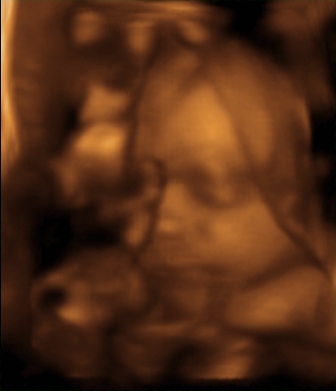

Ilyen képeket kaptam...

Gigi ezeket a képeket eddig nem mutattad meg???? :shock:

Gigi nagyon nagyon cuki a baba, szinte megszólal,és mikor csinálták, most a 21. héten?nekem azt mondták, a 24.-28. héten menjek, mert még túl vékony a baba most.